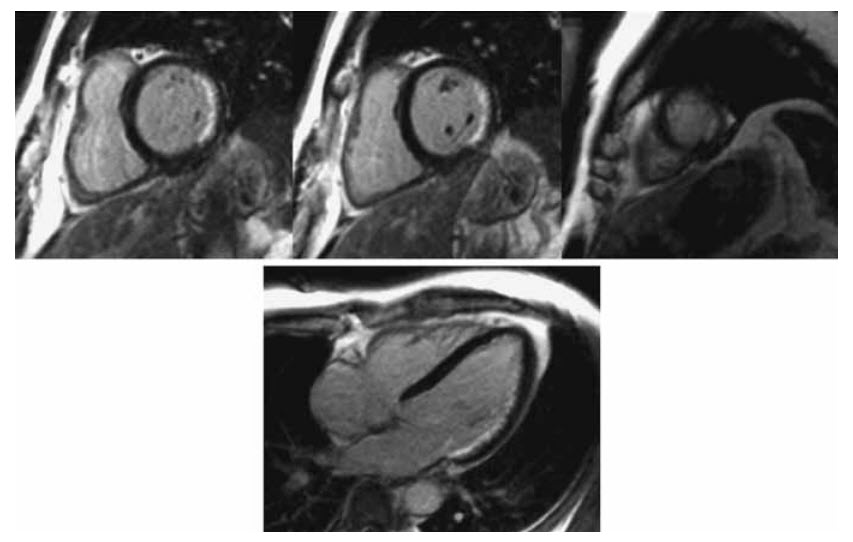

The late myocardial enhancement is shown below

Which of the following statements is correct?

A. The LAD territory is non-viable

B. The entire lateral wall is infarcted

C. The RCA territory is non-viable

D. Both LAD and RCA territories show >50% wall-thickness infarction

E. There is right ventricular infarction